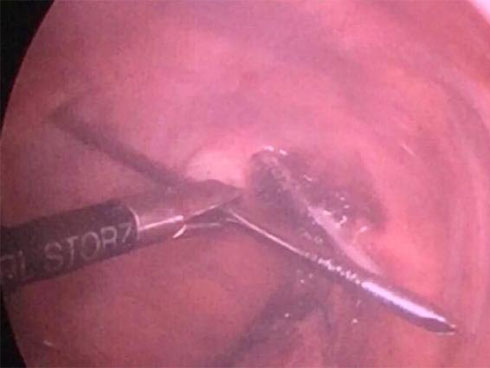

Các bác sĩ tiến hành nội soi lấy trọn chiếc đinh nhọn 12cm ra khỏi cơ thể bệnh nhân.

Sau khi hội chẩn xin ý kiến nhiều chuyên gia, các bác sĩ Chấn thương chỉnh hình đã quyết định phẫu thuật cho bệnh nhân. Kíp phẫu thuật phối hợp giữa chuyên khoa Chấn thương chỉnh hình - Cột sống và chuyên khoa Phẫu thuật lồng ngực tim mạch đã quyết định sử dụng phương pháp mổ nội soi để rút đinh thay vì mổ mở vào lồng ngực như các tác giả nước ngoài. Tận dụng lợi thế phẫu thuật nội soi ít gây tổn thương thêm cho các phần mềm xung quanh và hình ảnh qua camera được phóng to giúp kiểm soát chảy máu và kiểm soát tổn thương tuỷ sống, dò dịch não tuỷ dễ dàng hơn.

"Sau 20 phút vô cùng căng thẳng, chiếc đinh được gỡ ra khỏi nhu mô phổi và nhẹ nhàng rút ra khỏi tuỷ sống một cách an toàn, không gây tổn thương tuỷ sống và hệ thống mạch máu xung quanh tuỷ. Lỗ rút đinh chảy 1 chút dịch não tuỷ được bịt kín lại"- BS. Kiên thông tin.